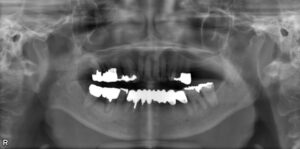

上下臼歯5本欠損症例

BEFORE AFTER 60歳女性/上下5本/インプラント埋込手術 【治療内容】 右側上下臼歯のお痛みを主訴に来院され…